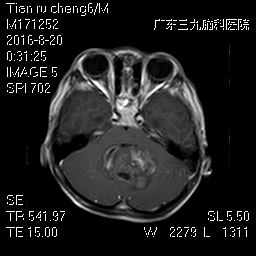

入院的当天,微侵袭神经外科的吴杰主任为阳阳完善了所有的检查及术前准备,并急诊实施了右侧脑室钻孔外引流术。术后阳阳复查,颅脑MRI提示:1、小脑蚓部占位性病变,考虑髓母细胞瘤可能性大(如图1);2、幕上梗阻性脑积水,并脑室周围间质性水肿(如图2);全脊髓MRI提示:胸腰段软脑膜线样高信号影,考虑肿瘤种植转移(如图3)。

图2:MRI提示小脑蚓部占位,不均匀强化;